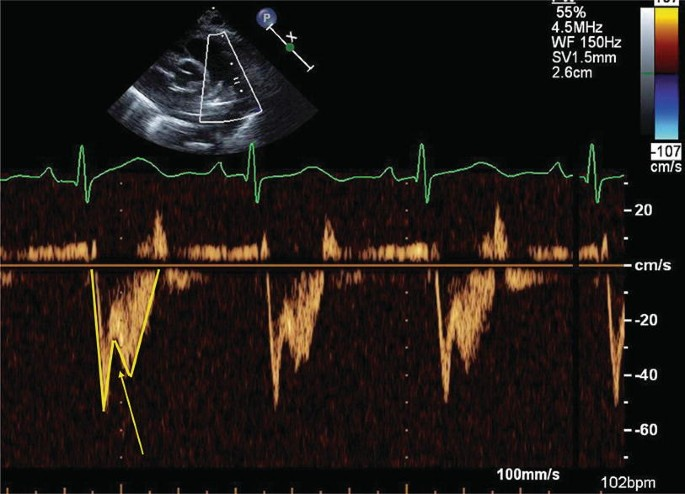

Flying w sign

What is seen in the m-mode image?

Pulmonary HTN

What diagnosis is consistent with this spectral Doppler?

What sign is seen?